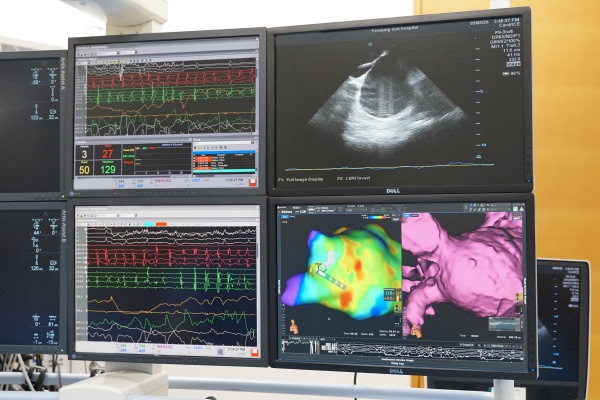

리드미아는 심방세동의 근본적 치료법인 전극도자 절제술 시행 전, 심장에서 발생하는 전기 신호를 감지해 원인 부위를 3D 고화질 영상으로 등고선 같이 보여준다. 전극도자 절제술을 시행하려면 이 매핑 과정을 반드시 거쳐야 한다.

리드미아에는 △생체전기 임피던스(신체에 미세한 전류를 통과시켜 정보를 얻는 방법)와 △마그네틱 트래킹(신체에 자장이 형성되고 전극도자 끝에 센서가 부착되어 도자 위치를 파악하는 기술) 2가지 기술이 함께 탑재돼 있어 기존의 매핑 시스템보다 해상도가 높고 해부학적 구조가 세밀하다.

특히 리드미아와 함께 사용되는 오라이온 카테터는 심장 내부의 전극 신호를 얻어 원인 부위를 찾는 데 기존 시스템보다 25배 이상 정밀하다. 정밀한 시스템 덕분에 원인 부위를 모두 보여줄 수 있고, 원인 부위에 정확히 접촉해 해당 부위를 빠르게 괴사시킬 수 있으며, 부정맥 유발 가능성이 높은 잠재적 원인 부위도 시술 할 수 있다.